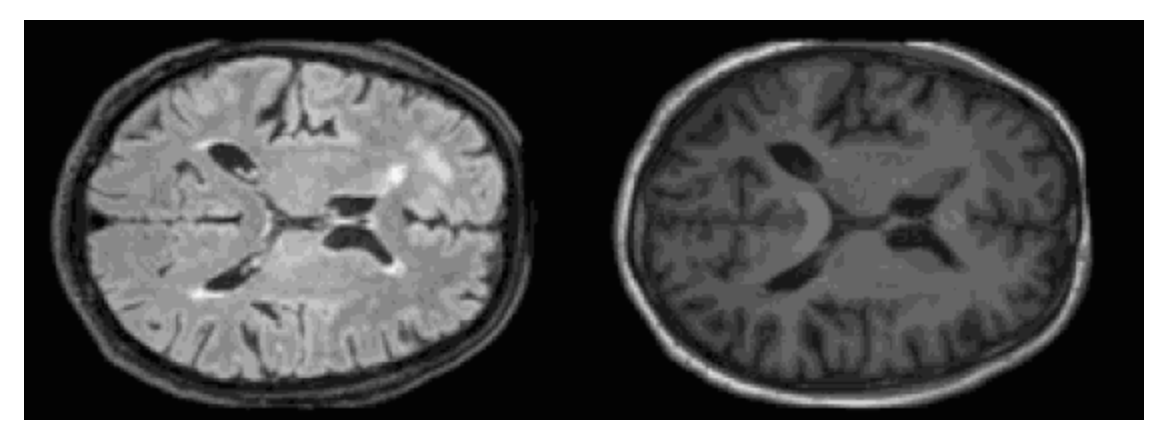

Medical imaging, from MRIs and CT scans to ultrasounds, is at the core of modern healthcare for diagnosis, treatment planning, and disease monitoring. Yet, this data is often scarce, costly to annotate, or restricted due to privacy concerns, making it difficult to train large foundation models. Synthetic medical images offer numerous benefits by addressing these challenges. Some of the methods to generate synthetic medical imaging data include GANs and diffusion models.

In medical imaging, GANs are widely used for image reconstruction across modalities such as MRIs, CT scans, X-rays, ultrasound, and tomography. Most of these modalities suffer from noisy, low-resolution, or blurry images, which hinder accurate diagnostics. GAN-based approaches, such as CycleGAN, CFGAN, and SRGAN, help improve resolution, reduce noise, and enhance image quality. Â